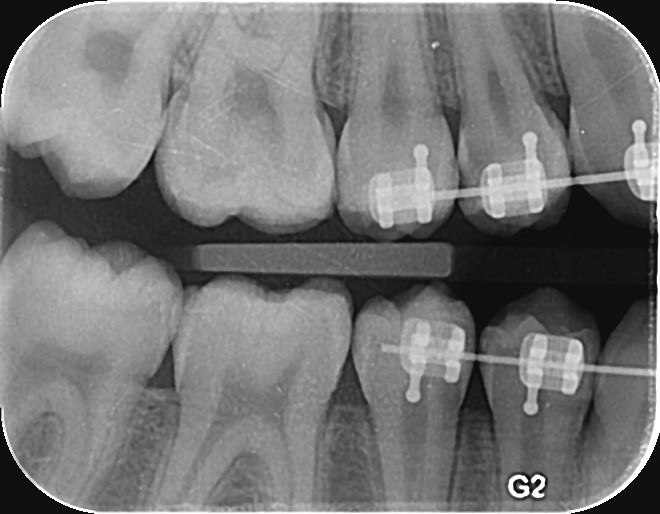

3. What surface require restoration?